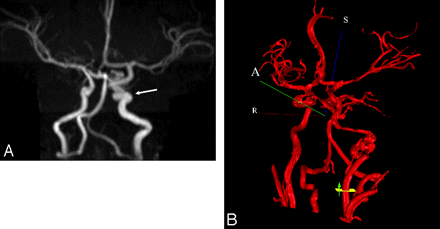

MRA was used to assess the cerebral vasculature in 13 patients, with additional conventional angiography performed in 2 of these patients. Cerebrovascular anomalies were the most common type of extracutaneous manifestation detected (On-line Table). Tortuous dysplastic vessels were seen most commonly (n = 7) in the vertebrobasilar system (6/7) and the internal carotid artery (ICA) (5/7) (Fig 4). The next most common anomalies were hypoplasia of the A1 segment of the anterior cerebral artery (n = 5), the presence of anomalous vessels (n = 4), and the persistence of embryonic vessels (n = 2). Persistent embryonic vessels included the trigeminal artery (n = 1) and the proatlantal artery and stapedial arteries in another patient. In 3 of the 4 cases of anomalous vessels, the vessels arose from the vertebrobasilar system.

A, Coronal maximum-intensity-projection reconstruction from intracranial time-of-flight MRA demonstrates an ectatic and tortuous appearance of the left precavernous and cavernous ICA (arrow). B, 3D MRA rendering from NOVA with flow measurement through the cervical left ICA. The left ICA at the skull base is markedly irregular and tortuous.